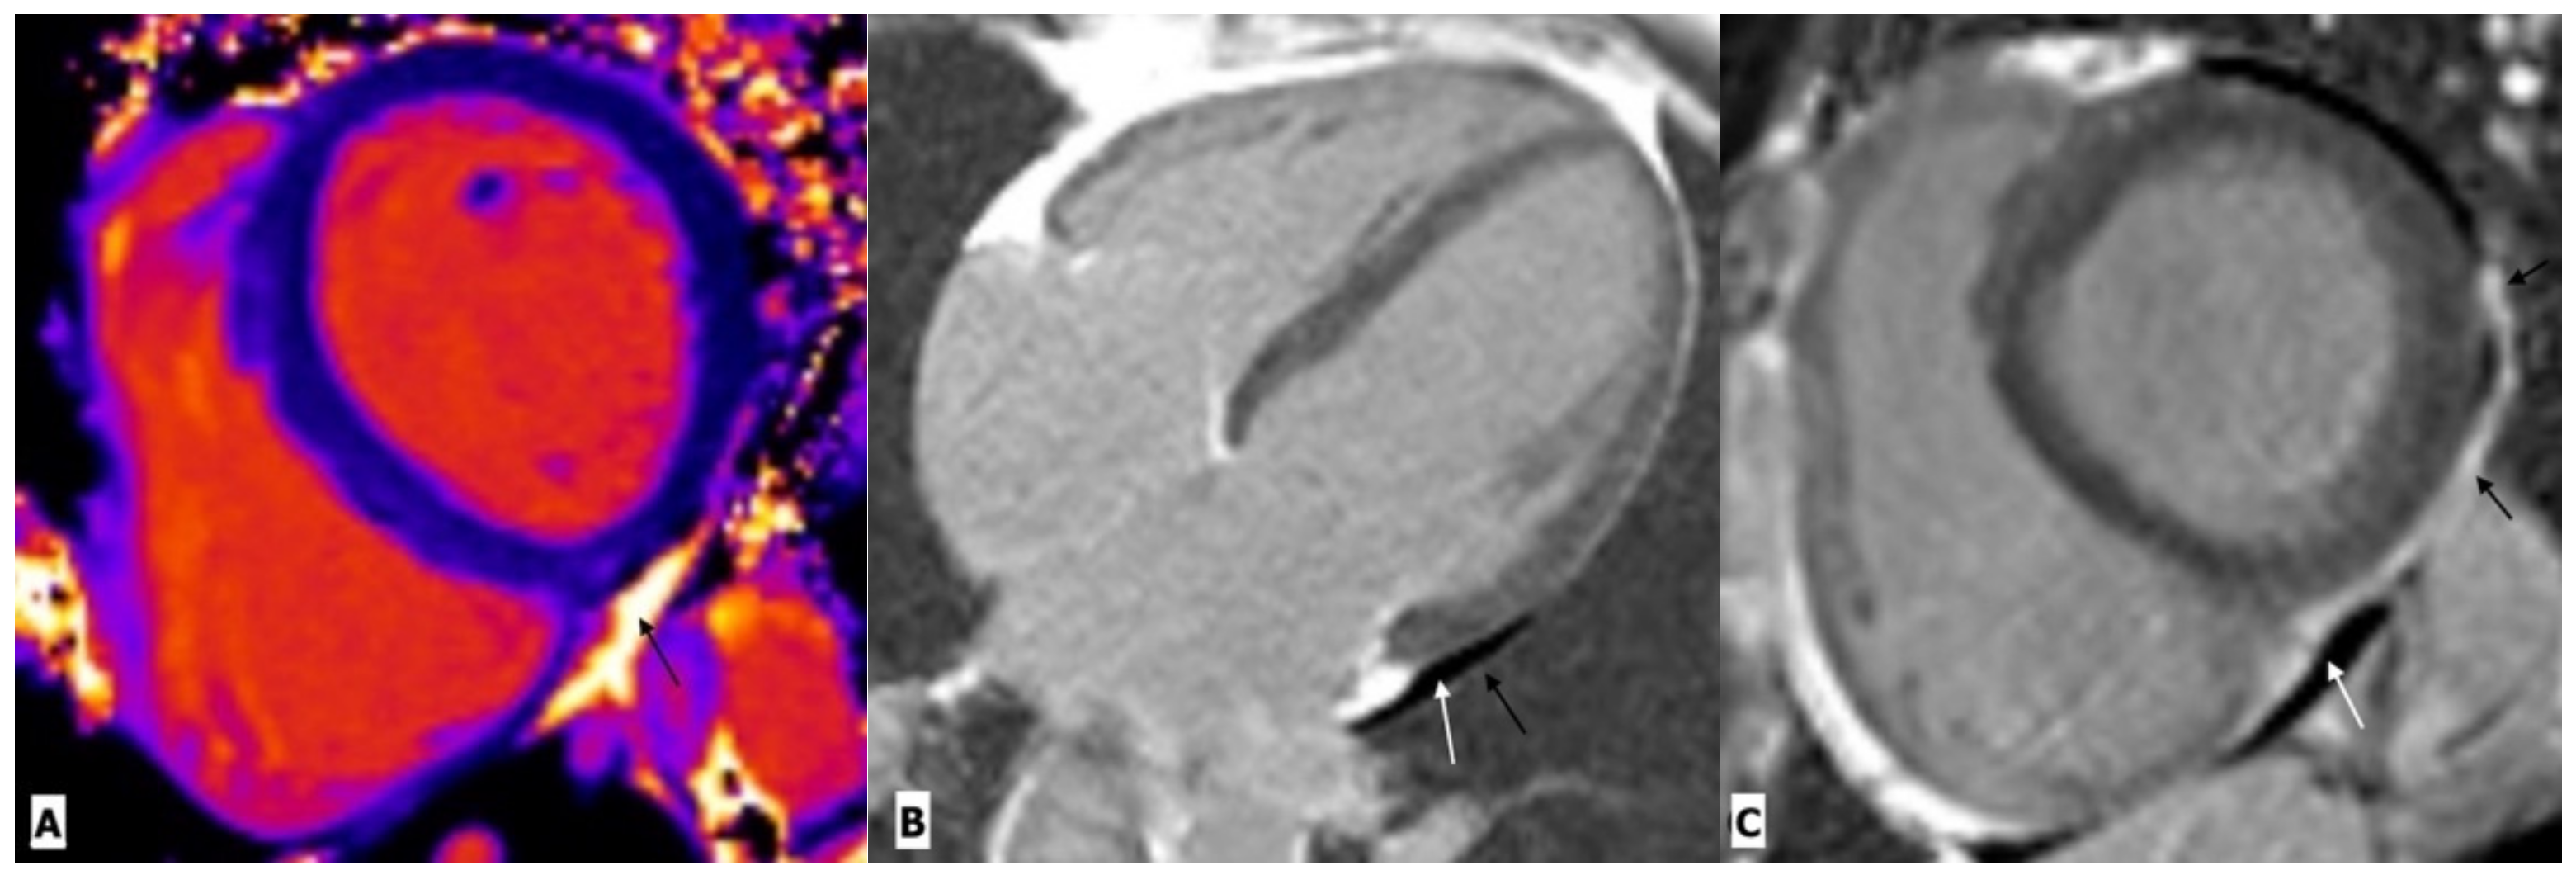

Figure 3.

Cardiac magnetic resonance imaging in a 38-year-old man with HIV-related pericarditis and pericardial effusion. (A) Mid-ventricular short-axis view T1 map showing high signal intensity pericardial effusion (black arrow). (B) Four chambers view and (C) mid-ventricular short-axis view gadolinium enhancement images showing mild pericardial effusion (white arrow) with thickening and enhancement of pericardium (black arrow) along the left lateral LV wall.